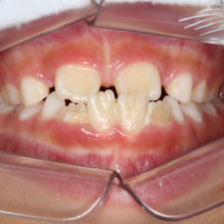

お子さまにとっても、親御さんにとっても、矯正治療は決して楽なものではありません。

だらだらと長期間治療をするのではなく、ベストなタイミングを見計らい、一気に治療を終わらせます。